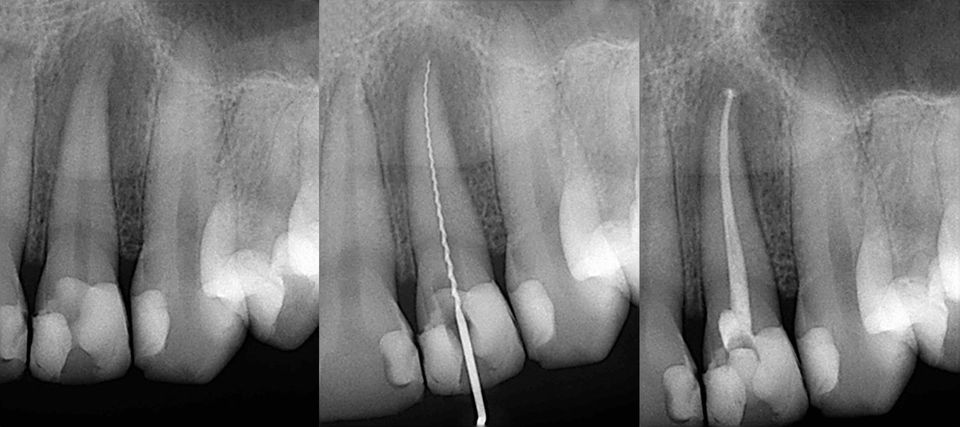

Root Canal Treatment

Root canal treatment (technically called endodontics) is needed when the pulp inside your tooth becomes infected through tooth decay or is damaged by an injury to your mouth. This infection may spread through the root canal system and could eventually lead to an abscess, causing a great deal of pain and discomfort. If root canal treatment is not carried out, the tooth may need to be removed.

The aim of root canal treatment is to remove all infection from the root canal.

The root is then cleaned thoroughly, sometimes over several appointments if necessary depending on the extent of the symptoms and infection. The canals are then filled with a robust filling material. Root Canal Treatment is a skilled and time consuming procedure. Most procedures will involve two or more visits to the dentist.

At the first appointment, the infected pulp is removed. Any abscesses, which may be present, can also be drained at this time. The root canal is then cleaned and shaped ready for filling. A temporary filling is placed in and the tooth is left to settle.

At the second appointment the tooth is checked and when all the infection has cleared, the tooth is permanently filled.